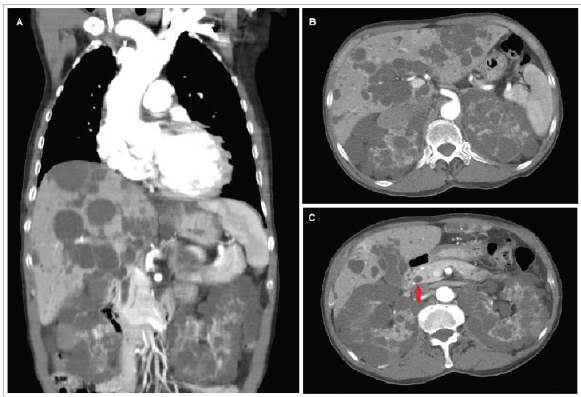

Hombre de 66 años con antecedente de insuficiencia cardiaca (IC), hipertensión arterial y en fermedad renal crónica ingresó al servicio de urgencias con síntomas de IC aguda descompensada. El ecocardiograma transtorácico mostró una insuficiencia aórtica severa. La angiografía coronaria mostró dilatación de la aorta ascendente (43 mm) y de la raíz aórtica. Una tomografía computarizada contrastada mostró múltiples lesiones quísticas > 5 mm en el hígado y los riñones (Figura 1 A y B); había un único quiste en la cabeza del páncreas (Figura 1 C). El paciente tenía niveles normales de enzimas hepáticas y un CA 19-9 elevado. Se diagnosticó una poliquistosis renal autosómica dominante (PQRAD). Se descartaron aneurismas en la circulación cerebral por angiografía. Al paciente se le reemplazó la aorta ascendente y la raíz aórtica y egresó con mejoría de sus síntomas. La PQRAD puede afectar al hígado y al páncreas, y puede estar relacionada con aneurismas en la aorta o las arterias cerebrales 1,2.

Figura 1 Tomografía simple y contrastada de abdomen A. Corte coronal que muestra dilatación de raíz aórtica y aorta ascendente, quistes en hígado y riñones. B. Corte transversal que muestra múltiples lesiones quísticas en parénquima hepático y de ambos riñones. C. Corte transversal que muestra quiste en cabeza de páncreas señalado por flecha roja y múltiples lesiones quísticas en parénquima hepático y renal.